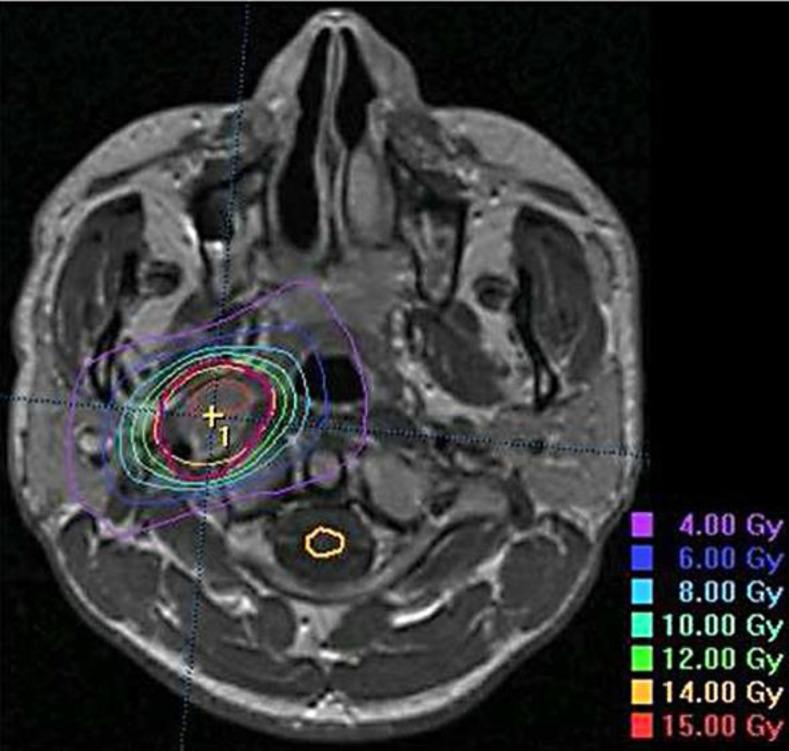

(18)F-FDG-PET is a valuable adjunct to conventional imaging for evaluating treatment response following stereotactic body radiotherapy (SBRT) for head and neck malignancies (HNM). The effect of treatment-related inflammation is generally deemed negligible after 12 weeks following conventionally fractionated radiotherapy. Herein, we describe an unusual case showing pseudoprogression on (18)F-FDG-PET 2 years after SBRT for retropharyngeal lymph node metastasis (RPLNm) from esthesioneuroblastoma. A 36-year-old man presented with right RPLNm 32 months after the diagnosis of esthesioneuroblastoma associated with ectopic adrenocorticotropic hormone production. The RPLNm was treated with SBRT in 2 fractions over 8 days using dynamic conformal arcs with concomitant chemotherapy with cisplatin and etoposide. Although follow-up MRI showed sustained lesion regression, the early/delayed maximum standardized uptake (SUVmax) values on dual-time-point (18)F-FDG-PET obtained 1 and 2 years after SBRT were 7.7/8.3 and 8.5/10.1, respectively, suggesting local progression. Despite no subsequent focal or systemic treatment, the SUVmax values gradually decreased thereafter over a period of 4 years (3.3/3.4 at 76 months). MRI obtained 7 years after SBRT revealed sustained tumor regression. No obvious relevant toxicities have occurred. Thus, caution should be exercised in the interpretation of the SUVmax change following ablative irradiation for HNM.

(18)F-FDG-PET是评估头颈部恶性肿瘤(HNM)立体定向体部放疗(SBRT)后治疗反应的传统成像的重要辅助手段。在常规分割放疗后12周,治疗相关炎症的影响通常被认为可忽略不计。在此,我们描述了一例不寻常的病例,该病例显示在针对嗅神经母细胞瘤的咽后淋巴结转移(RPLNm)进行SBRT治疗2年后,(18)F-FDG-PET出现假性进展。一名36岁男性在诊断为与异位促肾上腺皮质激素分泌相关的嗅神经母细胞瘤32个月后出现右侧RPLNm。使用动态适形弧在8天内分2次对RPLNm进行SBRT治疗,并同时使用顺铂和依托泊苷进行化疗。尽管随访MRI显示病变持续消退,但SBRT后1年和2年获得的双时相(18)F-FDG-PET上的早期/延迟最大标准化摄取值(SUVmax)分别为7.7/8.3和8.5/10.1,提示局部进展。尽管随后未进行局部或全身治疗,但此后SUVmax值在4年期间逐渐下降(76个月时为3.3/3.4)。SBRT后7年获得的MRI显示肿瘤持续消退。未发生明显的相关毒性反应。因此,在解释HNM消融放疗后的SUVmax变化时应谨慎。